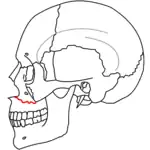

| Le Fort I fractures | |

At the beginning of the 20th century, René Le Fort mapped typical locations for facial fractures; these are now known as Le Fort I, II, and III fractures (right).[7] Le Fort I fractures, also called Guérin or horizontal maxillary fractures,[14] involve the maxilla, separating it from the palate.[15] Le Fort II fractures, also called pyramidal fractures of the maxilla,[16] cross the nasal bones and the orbital rim.[15] Le Fort III fractures, also called craniofacial disjunction and transverse facial fractures,[17] cross the front of the maxilla and involve the lacrimal bone, the lamina papyracea, and the orbital floor, and often involve the ethmoid bone,[15] are the most serious.[18] Le Fort fractures, which account for 10–20% of facial fractures, are often associated with other serious injuries.[15] Le Fort made his classifications based on work with cadaver skulls, and the classification system has been criticized as imprecise and simplistic since most midface fractures involve a combination of Le Fort fractures.[15] Although most facial fractures do not follow the patterns described by Le Fort precisely, the system is still used to categorize injuries.[5]